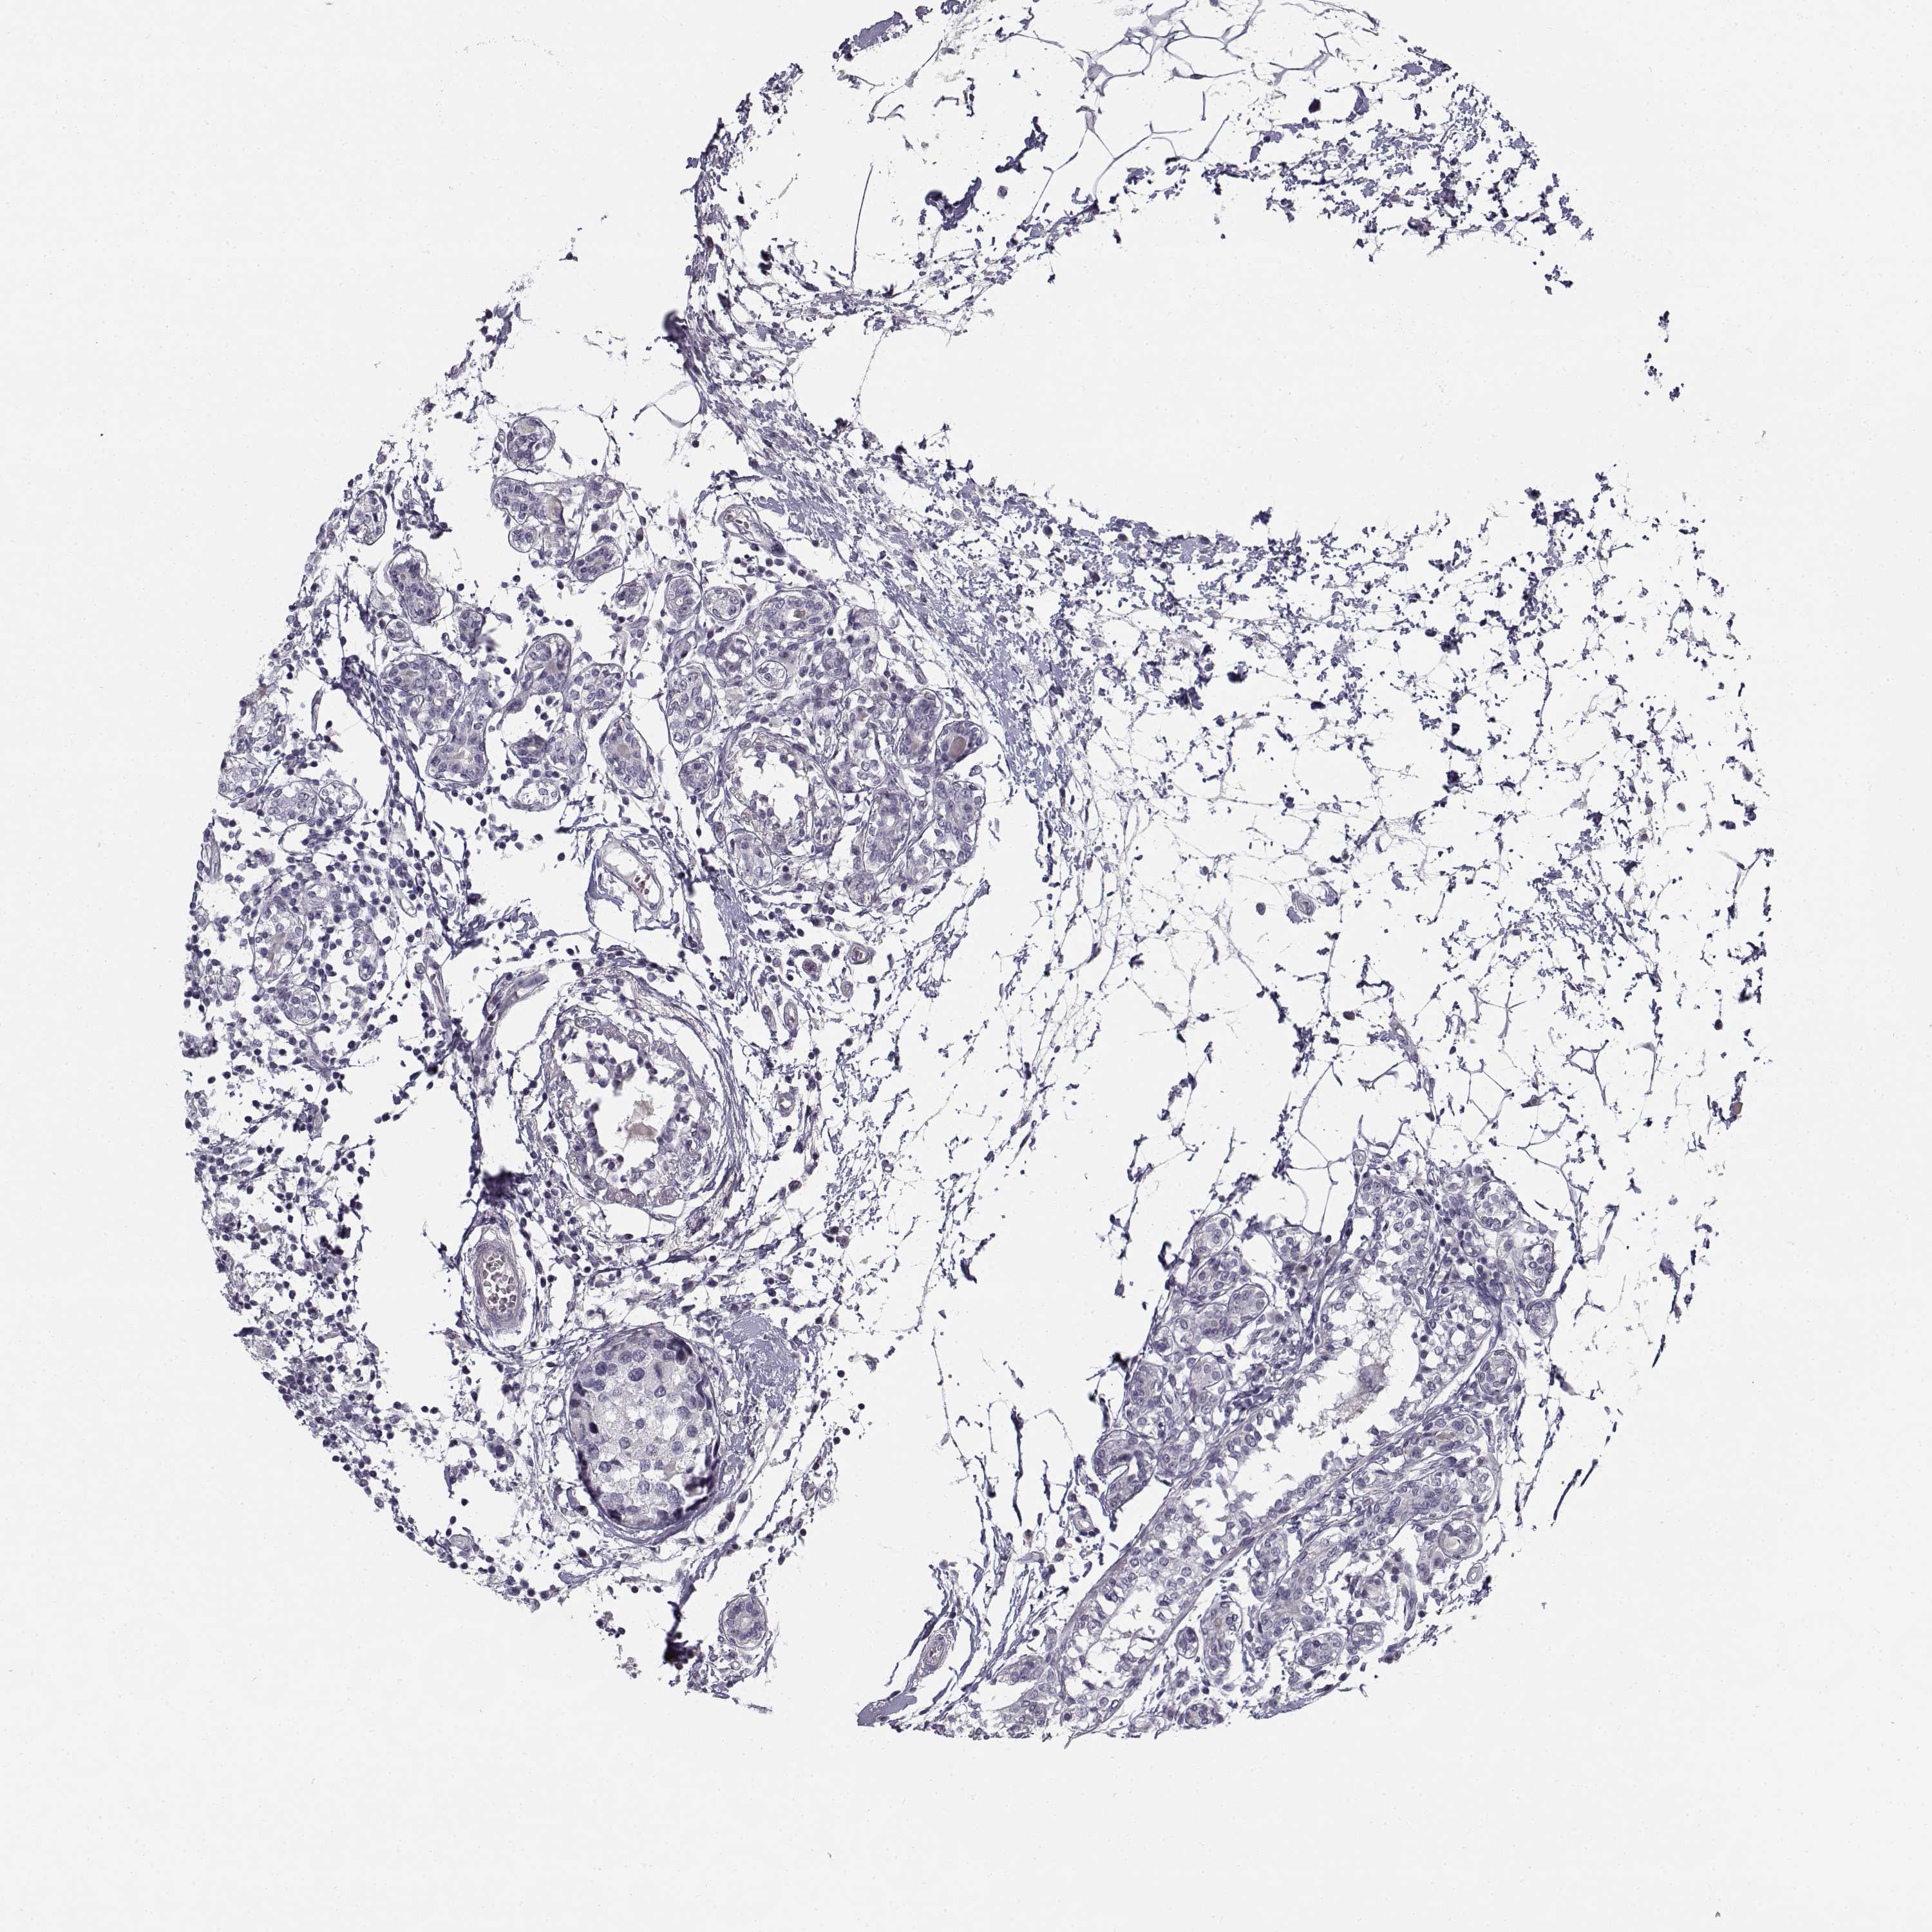

BRCA TCGA BRCA VALIDATION PROTEIN EXPRESSION

Breast cancer

Human cancer